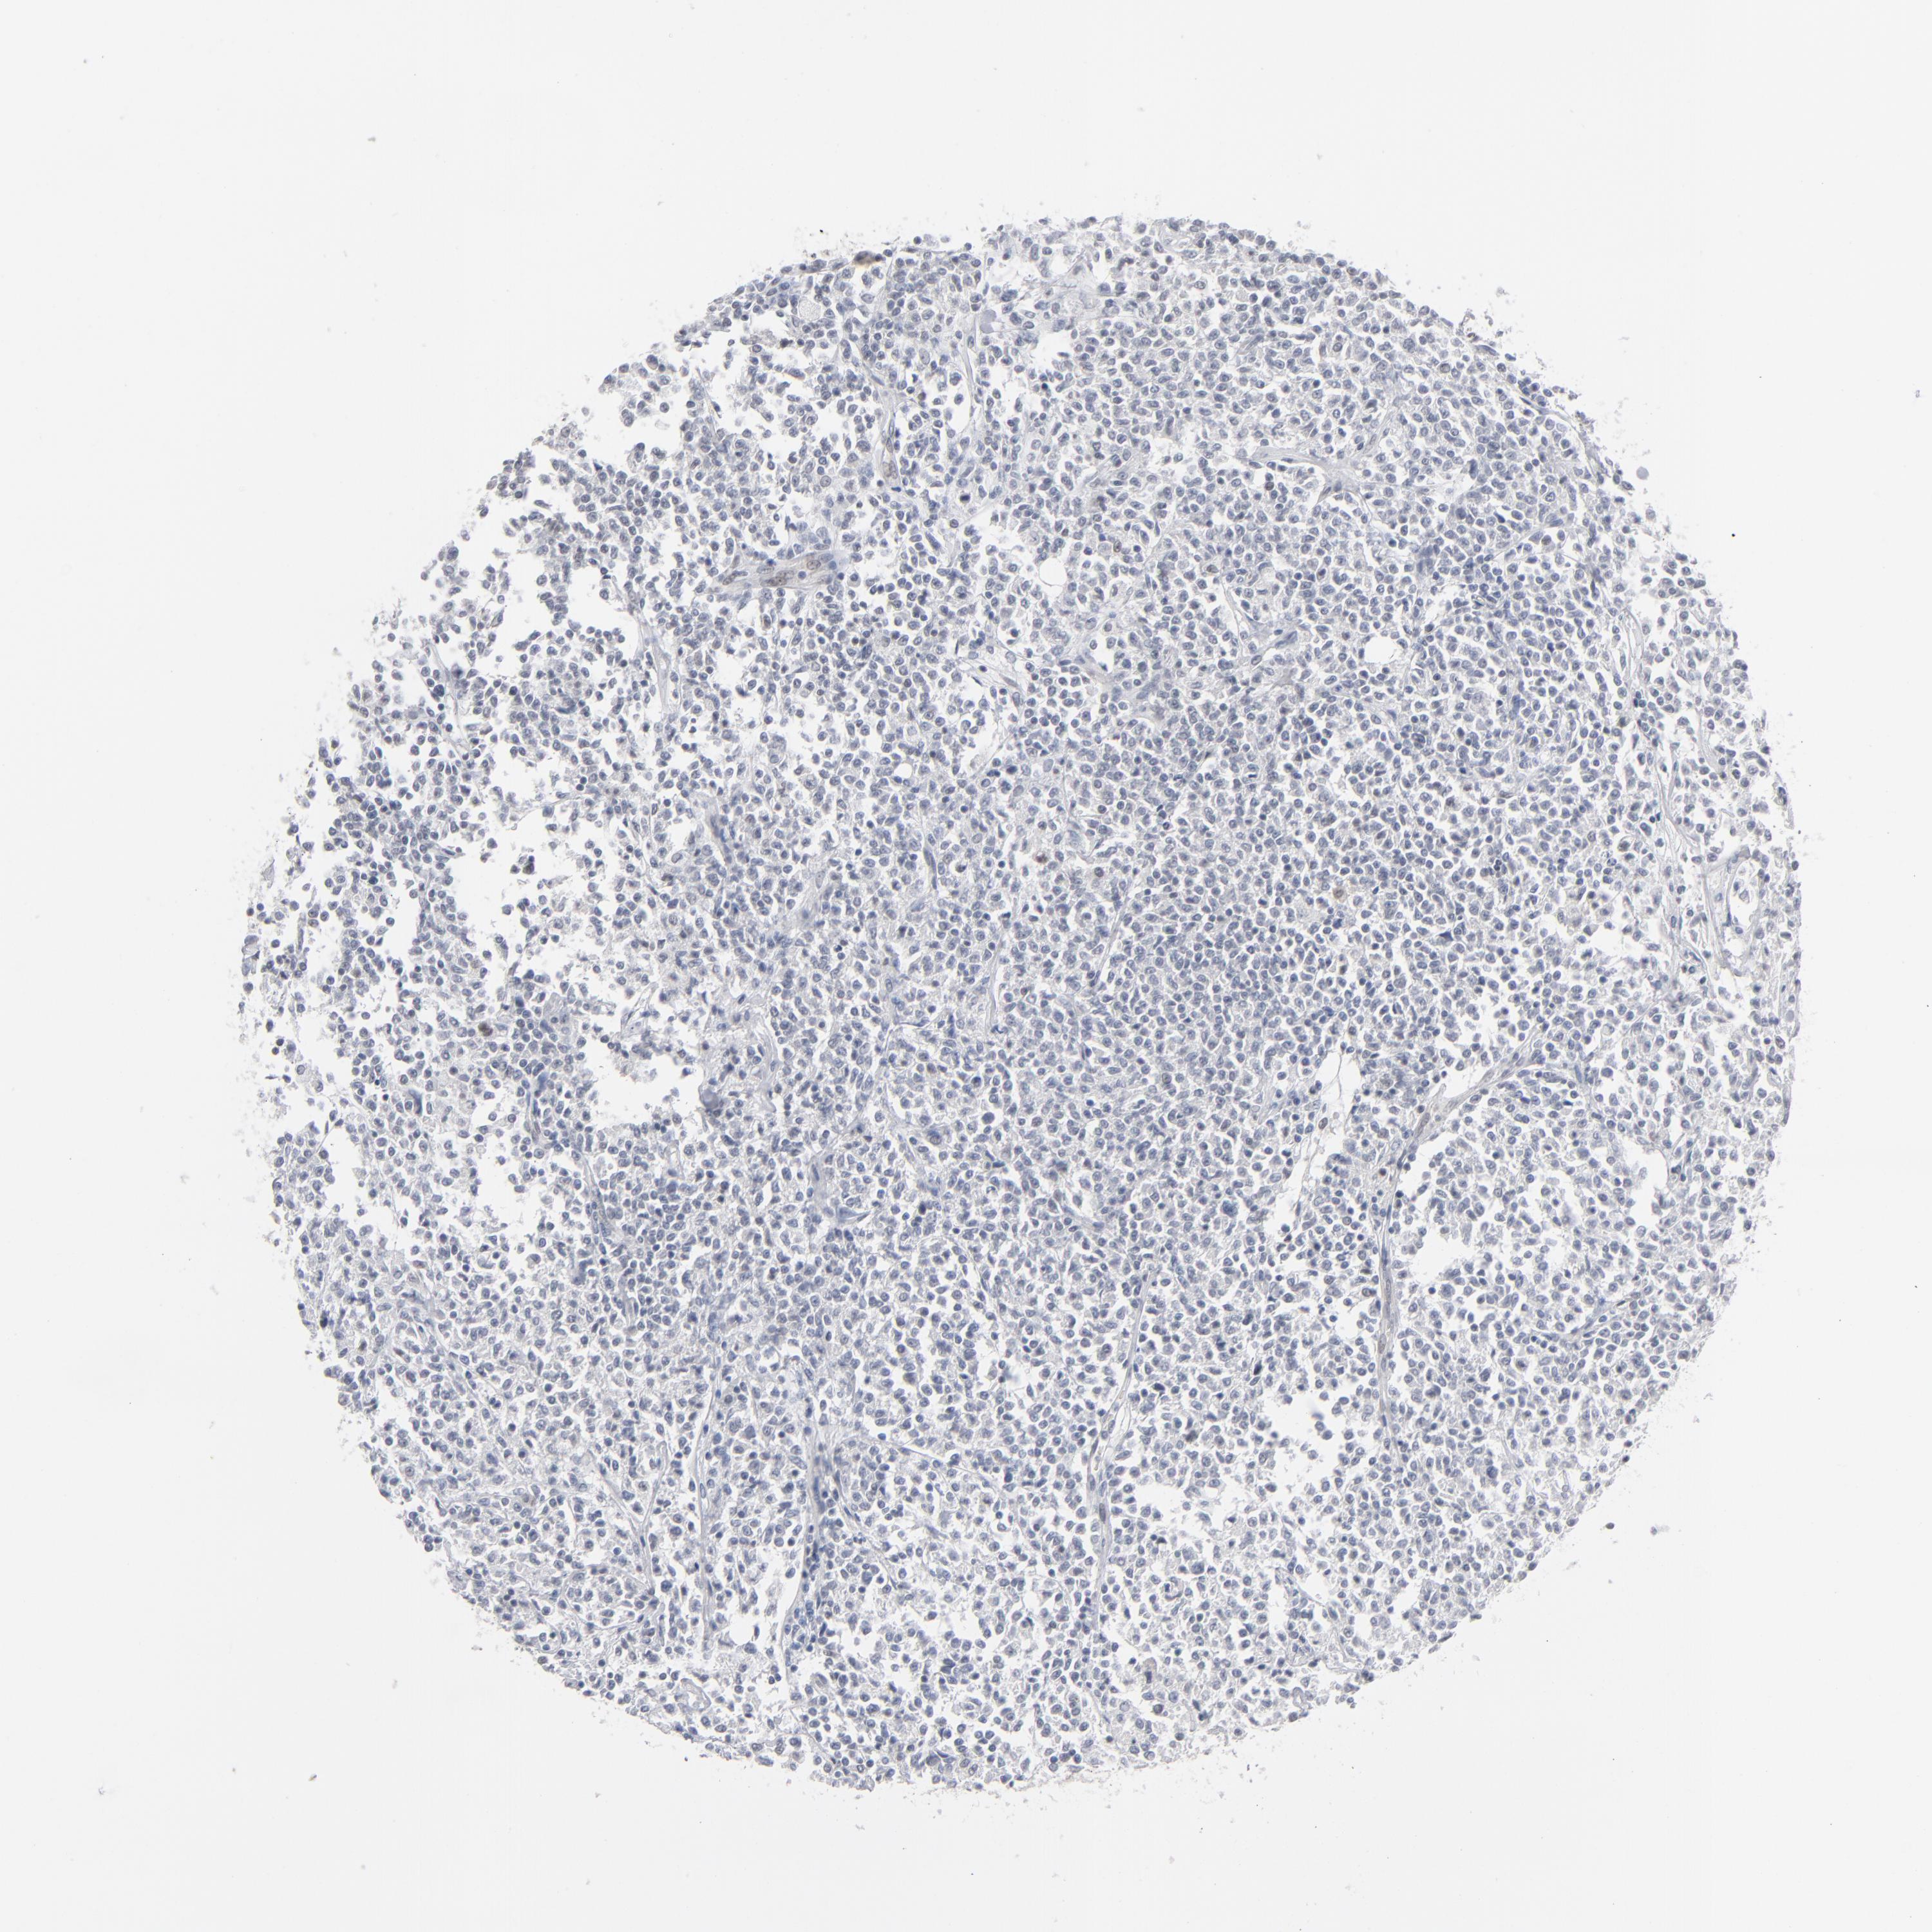

Antibody HPA001862

Staining

High

Medium

Low

Not detected

Intensity

Strong

Moderate

Weak

Negative

Quantity

>75%

75%-25%

<25%

None

Location

Nuclear

Cytoplasmic/membranous

Cytoplasmic/membranous,nuclear

Hodgkin's disease, NOS